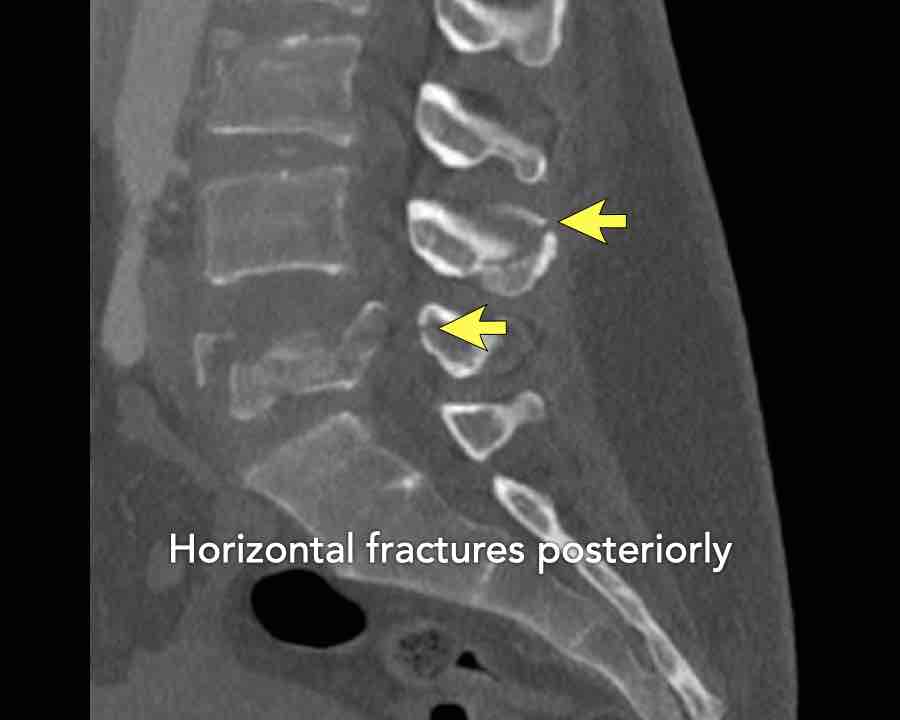

Continue with the next stack of images to classify level L2…

Scroll through images.

What is the highest AO-level?

Findings

- No dislocation ( no C type).

- Mainly horizontal fractures of spinous processus at multiple levels (B-type).

- Split fracture L2 (type A2).

Conclusion

Injury type B2 + A2 at level L2.